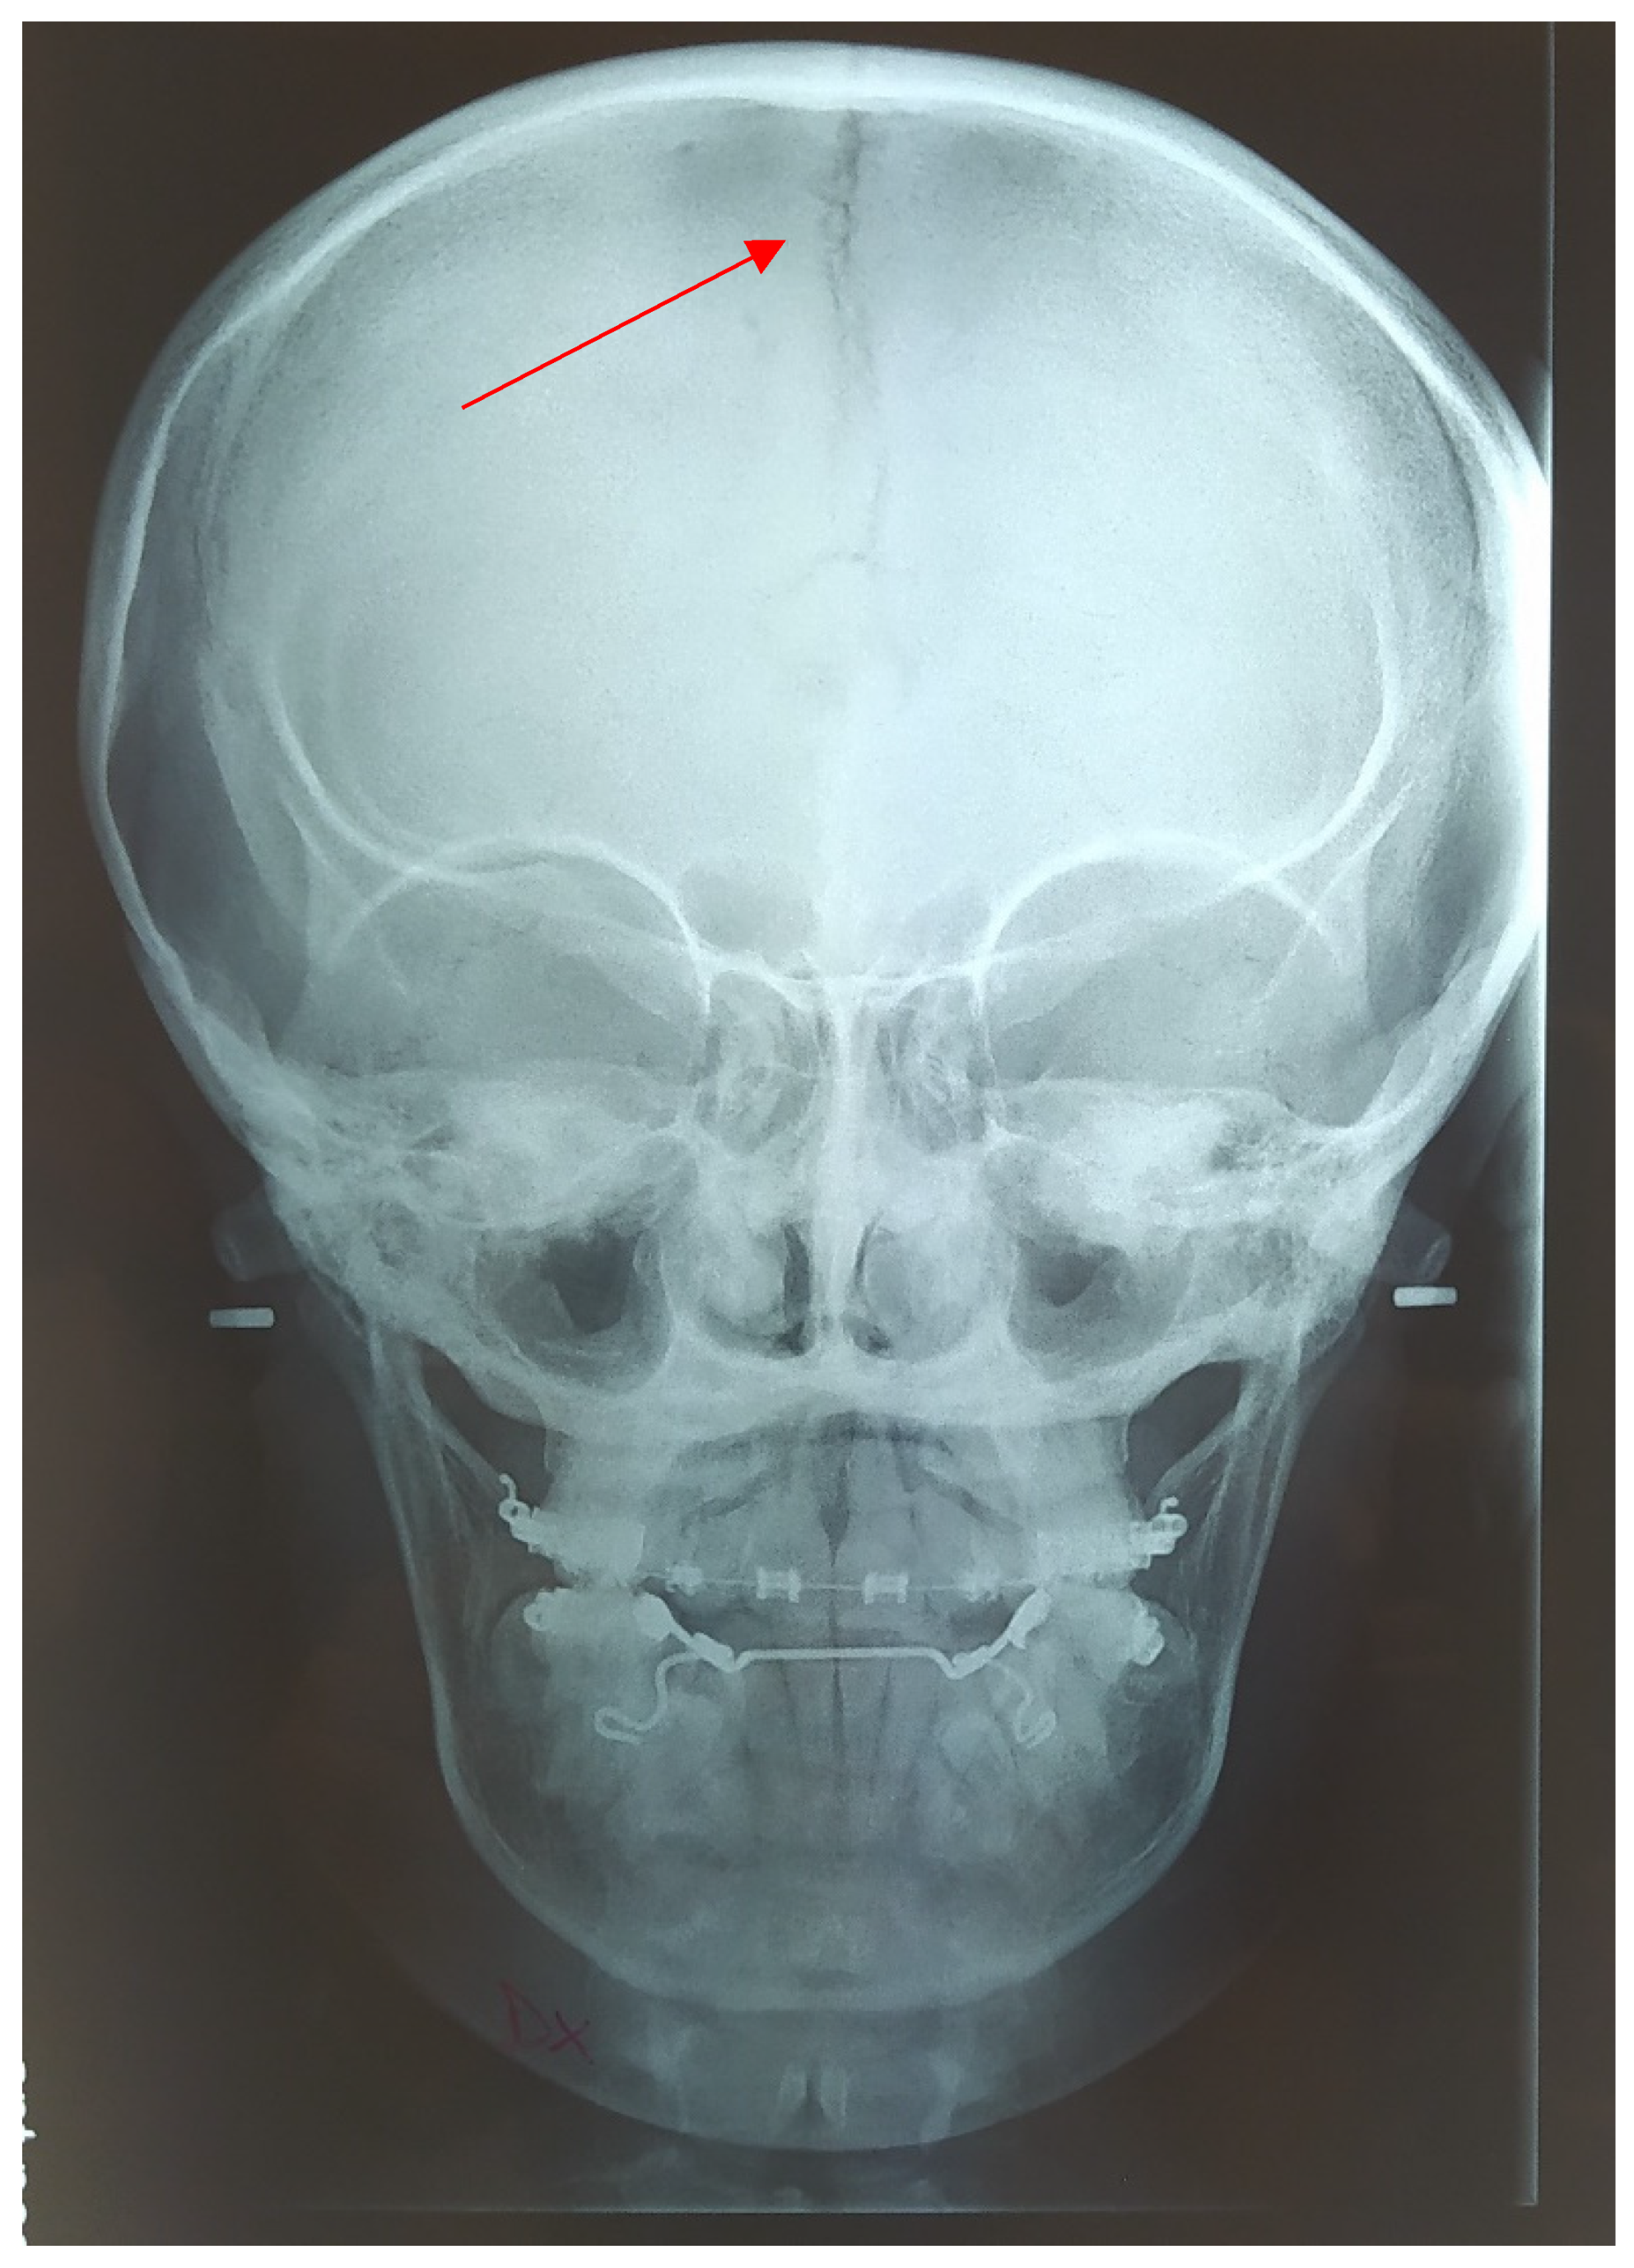

2. Clinical Report

2.1. Cephalometric Analysis